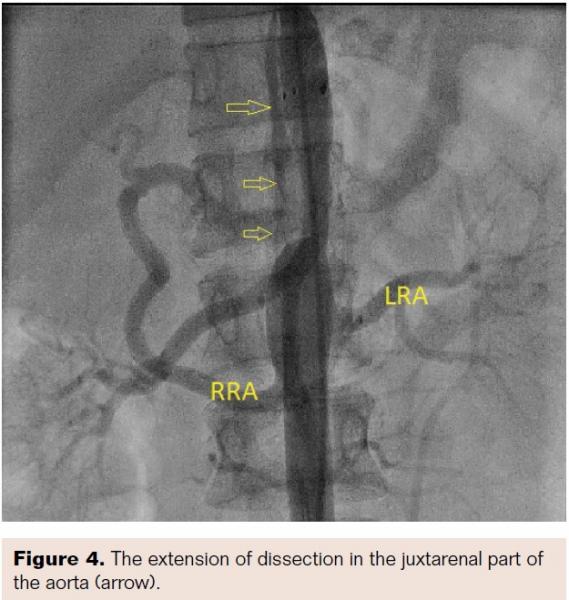

Aortogram confirmed areas of diffuse stenosis and ectasia in the thoracoabdominal aorta, with significant stenosis of the aorta at the level of intervertebral disc between T-11 and T-12 (Figure 2, Video 1). Informed consent for aortoplasty to control secondary hypertension was obtained. Using right femoral arterial access, the occluded segment was crossed using a straight-tip, exchange-length wire (Terumo) and 5 Fr multipurpose diagnostic catheter. The aortic lesion was dilated using an 8 mm x 4 cm Ravel balloon (Bard Peripheral Vascular) at 4 atm; this size was chosen because the narrowest lesion diameter was 5.2 mm (balloon to lesion ratio of 150%). The patient had mild back pain during and after dilation. The pull-back gradient reduced to 50 mm Hg. A dose of 100 mg intravenous tramadol was given. Immediately, a 12 mm x 6 cm E•Luminex self-expanding stent (Bard Peripheral Vascular) was deployed, as we had no covered stent available at the time of intervention. The pull-back gradient reduced further to less than 20 mm Hg. Repeat aortogram by pigtail catheter revealed extensive dissection of the aorta beyond the disease segment (Figures 3 and 4; Videos 2 and 3). No further dilation was attempted. The patient continued to have mild back pain. Beta-blocker was further reinforced by increasing the dose of atenolol to 100 mg twice daily. Her further hospital course was uneventful. At 12-month follow-up exam, the patient continued to be asymptomatic and her hypertension was under control.

Aortogram confirmed areas of diffuse stenosis and ectasia in the thoracoabdominal aorta, with significant stenosis of the aorta at the level of intervertebral disc between T-11 and T-12 (Figure 2, Video 1). Informed consent for aortoplasty to control secondary hypertension was obtained. Using right femoral arterial access, the occluded segment was crossed using a straight-tip, exchange-length wire (Terumo) and 5 Fr multipurpose diagnostic catheter. The aortic lesion was dilated using an 8 mm x 4 cm Ravel balloon (Bard Peripheral Vascular) at 4 atm; this size was chosen because the narrowest lesion diameter was 5.2 mm (balloon to lesion ratio of 150%). The patient had mild back pain during and after dilation. The pull-back gradient reduced to 50 mm Hg. A dose of 100 mg intravenous tramadol was given. Immediately, a 12 mm x 6 cm E•Luminex self-expanding stent (Bard Peripheral Vascular) was deployed, as we had no covered stent available at the time of intervention. The pull-back gradient reduced further to less than 20 mm Hg. Repeat aortogram by pigtail catheter revealed extensive dissection of the aorta beyond the disease segment (Figures 3 and 4; Videos 2 and 3). No further dilation was attempted. The patient continued to have mild back pain. Beta-blocker was further reinforced by increasing the dose of atenolol to 100 mg twice daily. Her further hospital course was uneventful. At 12-month follow-up exam, the patient continued to be asymptomatic and her hypertension was under control.